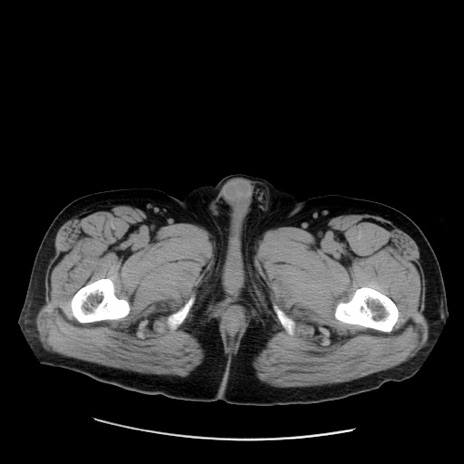

症例20(横断像)

【症例】 60歳代男性

【主訴】 腹部膨満、嘔吐

【現病歴】5日前頃より倦怠感を認め食事量減少し4日前の朝嘔吐、食事摂取困難となった。 3日前近医受診し点滴施行され整腸剤などを処方された。 当日他院を受診し、腹部膨満著明、炎症反応の上昇(CRP10.8、WBC11200)あり、紹介受診となる。

【身体所見】 意識JCS1 受け答えがはっきりしないBP 111/57mHg、 P 67bpm、、BT35.2°C、SpO2 97%(RA)、 腹部:膨隆、打診で鼓音あり、全体的に圧痛有り、腸蠕動音(-)、反跳痛ははっきりせず。

【データ】WBC 11400、CRP 14.20